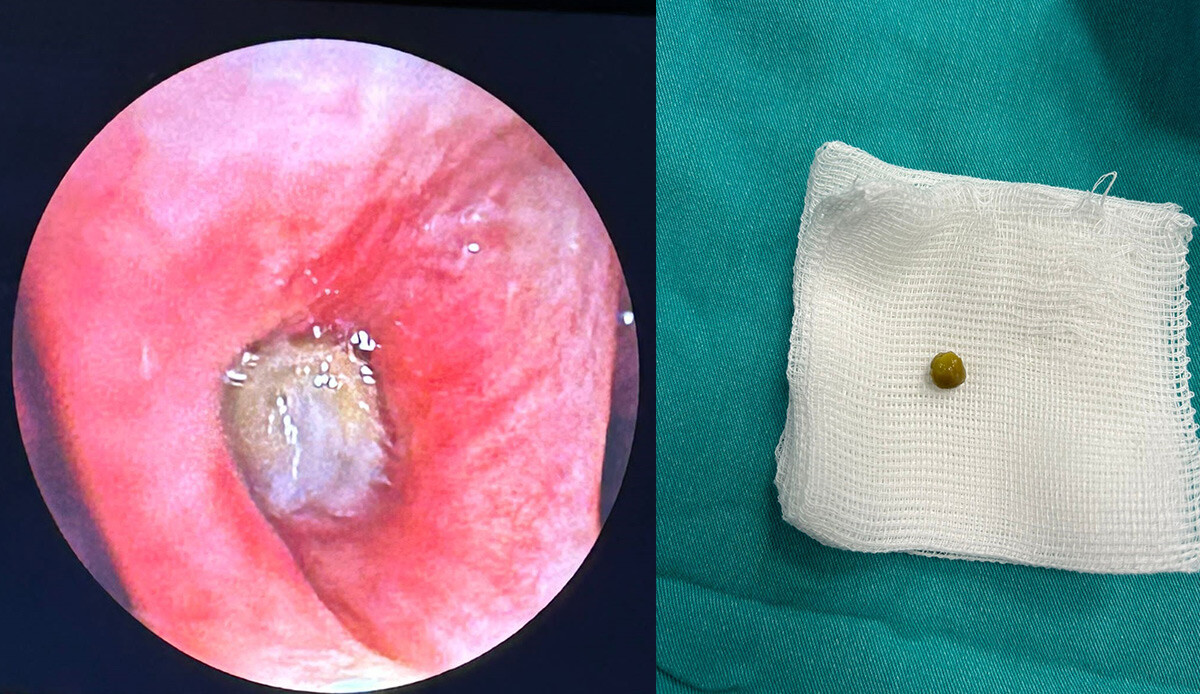

Hazırlıkları tamamlanan 69 yaşındaki Timur Yurteri, coil uygulaması öncesi Göğüs Hastalıkları Anabilim Dalı Öğretim Üyesi Doç. Dr. Erhan Uğurlu tarafından değerlendirmeye alındı. Doktor, hava yollarını görüntülemek için yapılan fiberoptik bronkoskopi işlemi sırasında beklenmeyen bir görüntü ile karşılaştı. Hastanın sağ akciğerinde, bulunduğu hava yolunu kapatan bezelye tanesi görüldü.

Uygun malzeme ve manevra ile tecrübeli ekip tarafından tamamen çıkarılabilen bezelye tanesi Yurteri’yi de şaşırttı. Başarı ile tamamlanan yabancı cisim çıkarma işlemi sonrası hastaya bronkoskopik volüm küçültücü coil uygulaması yapıldı.

Başarılı geçen iki işlem sonrası bilgi veren Doç. Dr. Erhan Uğurlu, “Aspirasyon denilen akciğere yabancı cisim kaçmasının genellikle çocuklarda beklense de düşük oranda yetişkinlerde de görülebiliyor. Bezelye tanesi olması nedeniyle küçük bir hava yolunda tıkanıklığa yol açarak hastada bulgu vermeyen yabancı cisim aspirasyonlarının öksürük, balgam, hırıltı gibi yakınmalara, zatürre, akciğerde sönme gibi istenmeyen durumlara da yol açabilir. Hem KOAH’a yönelik bronkoskopik volüm küçültücü coil tedavisi gerçekleştirilen hem de akciğerine kaçan bezelye tanesi çıkarılan hasta, işlemleri sonrası izleminde sorun görülmedi. Hastayı kontrollerine gelmek üzere taburcu ettik” dedi.